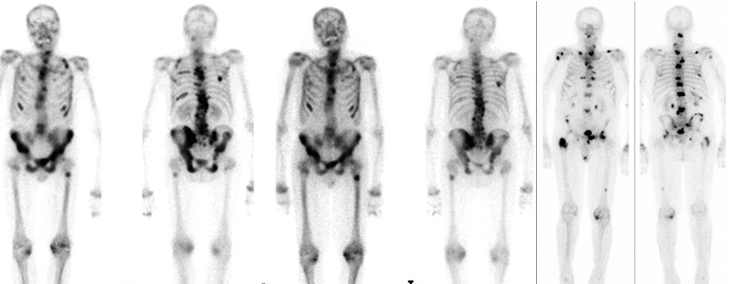

Radionuclide bone pain palliation is a radionuclide therapy used for reducing pain due to cancer that has spread to the bone. The radionuclide therapy agent used is targeted to the site of bone metastases after an intravenous injection. This delivers a small amount of radiation to the bone metastases, leading to small amount of cancer shrinkage and reduction of pain due to the bone metastases.

Bone pain palliation therapy is most commonly used in patients with metastatic prostate, breast and lung cancer. However, it can be given in all patients which satisfy the criteria governing the use of this therapy.